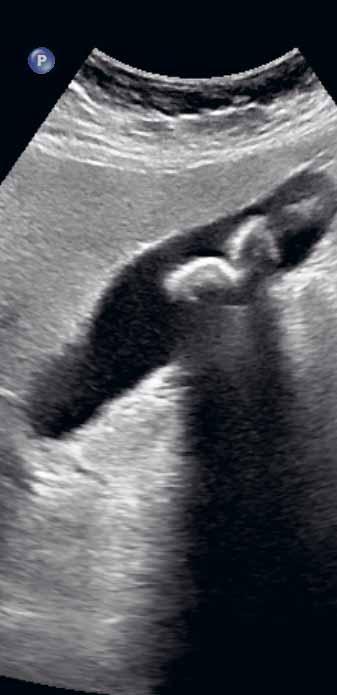

Obr. 1.1 Postprandiální kontrakce žlučníku